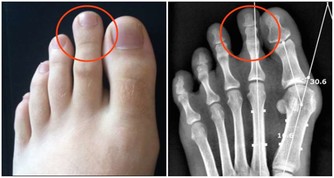

1.如果感覺到了肩周炎的典型症狀:肩膀疼痛、關節活動受限,

但同時還有低熱、盜汗、乏力、臉色蒼白、消瘦等症狀,要提防肩關節結核。